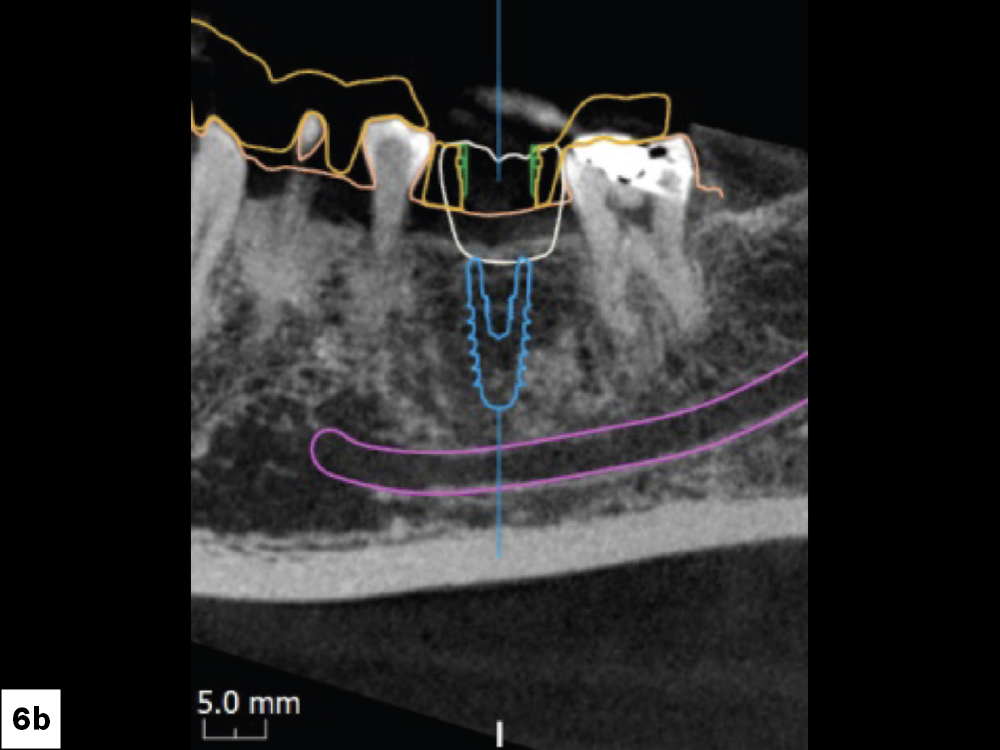

CBCT Scan Confirming Mixture of D3-D4 Bone

Figures 6a, 6b: Further analysis of the CBCT confirmed that this patient had a mixture of D3–D4 bone, which is commonly found in the posterior mandible. While D3 bone is good for implant placement, D4 is less dense and is likely to have lower primary stability. Glidewell HT Implants (Glidewell Direct) worked well in this scenario because their tapered body condenses bone and the deep threads maximize engagement, both of which support implant integration. Because of the bone density, I decided I would not immediately load the implant and instead waited four months for integration before placing the screw-retained crown — which I chose over a cement-retained crown due to ease of delivery.